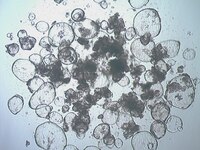

SCC315 Sigma-Aldrich3dGRO™ Colon Intestinal Organoids, Age 45 (Prep 83-C)

| Material Size | ≥1500 viable organoids/vial |